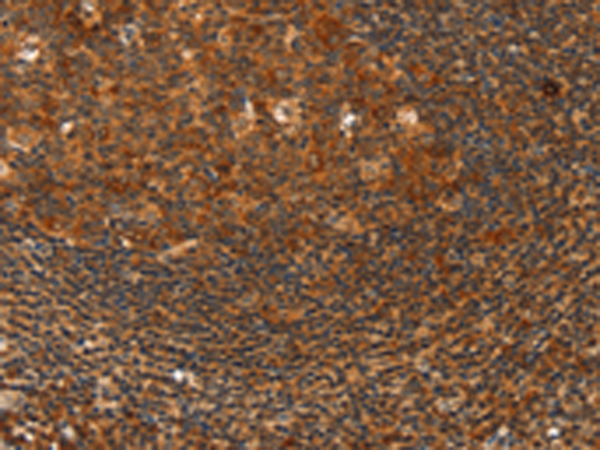

分类: 科研抗体货号: P07326别名: HLP; CCPI; CGL1; CSPB; SECT; CGL-1; CSP-B; CTLA1; CTSGL1应用: IHC反应种属: Human